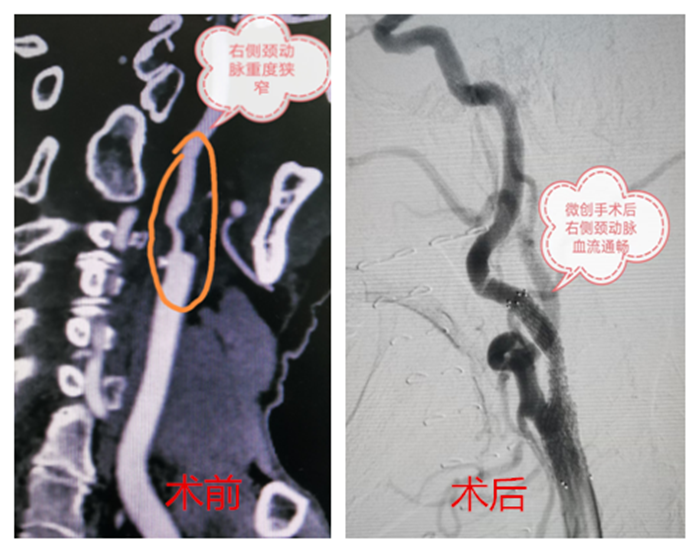

血管外科接診醫(yī)生程國(guó)兵仔細(xì)問(wèn)詢并完善相關(guān)檢查,經(jīng)頸動(dòng)脈CT血管成像提示:右頸內(nèi)動(dòng)脈起始段少量混合斑,管腔中重度狹窄。頭顱磁共振提示:右側(cè)急性腦梗。

在科主任陸煒的帶領(lǐng)下,血管外科診療團(tuán)隊(duì)為祝老先生行“超選擇性右頸動(dòng)脈造影+支架植入球囊擴(kuò)張術(shù)”。在非插管全麻下,穿刺右股動(dòng)脈,置入動(dòng)脈鞘,導(dǎo)絲通過(guò)動(dòng)脈鞘進(jìn)入右頸總動(dòng)脈,在右頸動(dòng)脈狹窄段遠(yuǎn)3厘米處放置保護(hù)傘導(dǎo)絲,沿著導(dǎo)絲放置球囊,用球囊壓力泵擴(kuò)張狹窄段,退出球囊后,在狹窄段成功置入支架。短短一個(gè)小時(shí),手術(shù)順利完成。